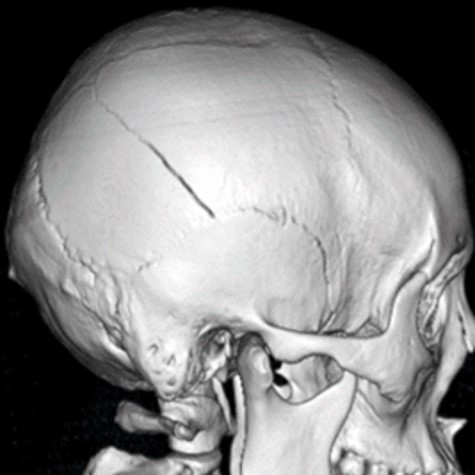

頭部に外力が加わることで、頭蓋骨とその内側にある脳をおおう硬い膜(硬膜)の間に出血し、形成された血腫によって脳が圧迫される状態です。多くは頭蓋骨の線状骨折や陥没骨折にともなって発生します。

■CT検査:頭部CT検査で評価します。頭蓋骨骨折の状況、ならびに硬膜外血腫の場所・血腫量、脳への圧排程度を評価することができます。数十わから数時間の経過で急激に症状が悪化することもあり、その都度CTによる評価を行い、手術が必要か検討する必要があります。